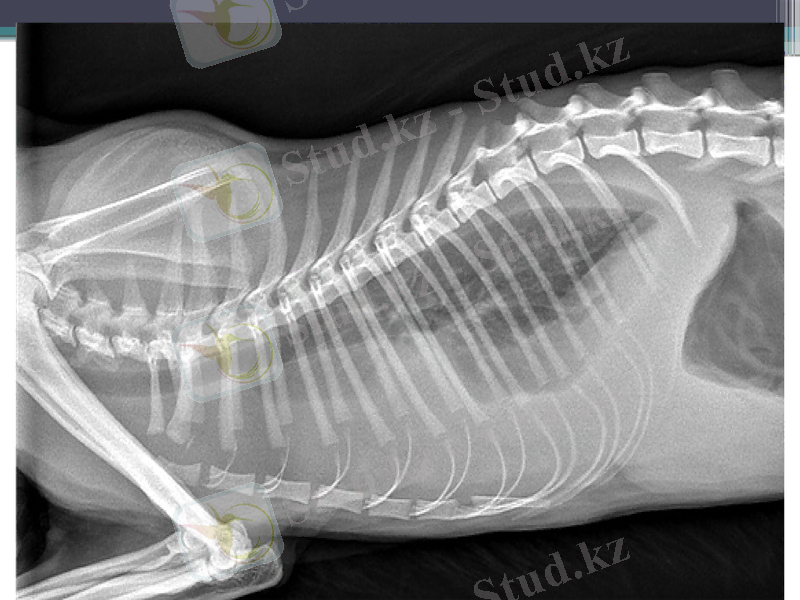

Остеохондроз - сүйек және шеміршектердің қабынуы. Остеохондроз туберкулез ауруынан немесе сүйектер мен буындарға іріңді инфекцияның түсуінен пайда болады. Ауыр дене еңбегі мен шағын жарақаттар және салқын тиіп ауыру факторлары остеохондрозды асқындыра түседі. Бұндай ауруға шалдыққан жануарлардың сүйектері мен буындары сырқырап ауырады. Әсіресе, омыртқааралық дискілерде дистрофикалық процесс жүреді. Жануардың жүріп-тұруы қиындайды. Көбінесе бұндай жағдай бел омыртқа остеохондрозында байқалады. Оны рентгендік диагностика арқылы анықтайды

Рахит. Бұл аурудың пайда болу себебі, жас төлдерде Д витаминнің жеткіліксіздігі. Д витамині жетіспеу салдарынан кальцийдің ішектен қанға сорылуы және келуі бөгеледі. Сөйтіп гипокальцемия, фосфатемия және гиперфосфатоурия басталады. Мұның өзі кальций мен фосфор тұздарының жиналуына бөгет жасайды. Клиникалық тұрғыда бұл сүйектену процестерінің бұзылуы білінеді (аяқтары қисаяды, кеуде сүйегінің формасы өзгереді т. б. )